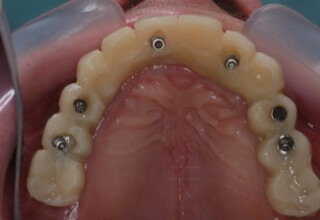

Lower jaw: extractions, direct implant placement and immediate loading (same day) with a transitional bridge.

Upper jaw: Sequential extractions, sequential implant placement and gradual incorporation in the temporary bridge so that the patient was never left without fixed teeth. The aim of the above approach was to have the patient in continuous functional and aesthetic reconstruction, without immediate loading due to anatomical restrictions. Old smiling photos of the patient were used because the natural shape of the teeth was completely lost due to repetitive prosthetic attempts. Tooth relationship and teeth-lip support was transferred to the temporary restorations. Two different transitional bridges were needed to fully estimate phonetics, mastication and esthetics. After the necessary adjustments were finalized, the temporary bridge was used as a guide for the permanent bridges.

Initial

Intermediate

Final